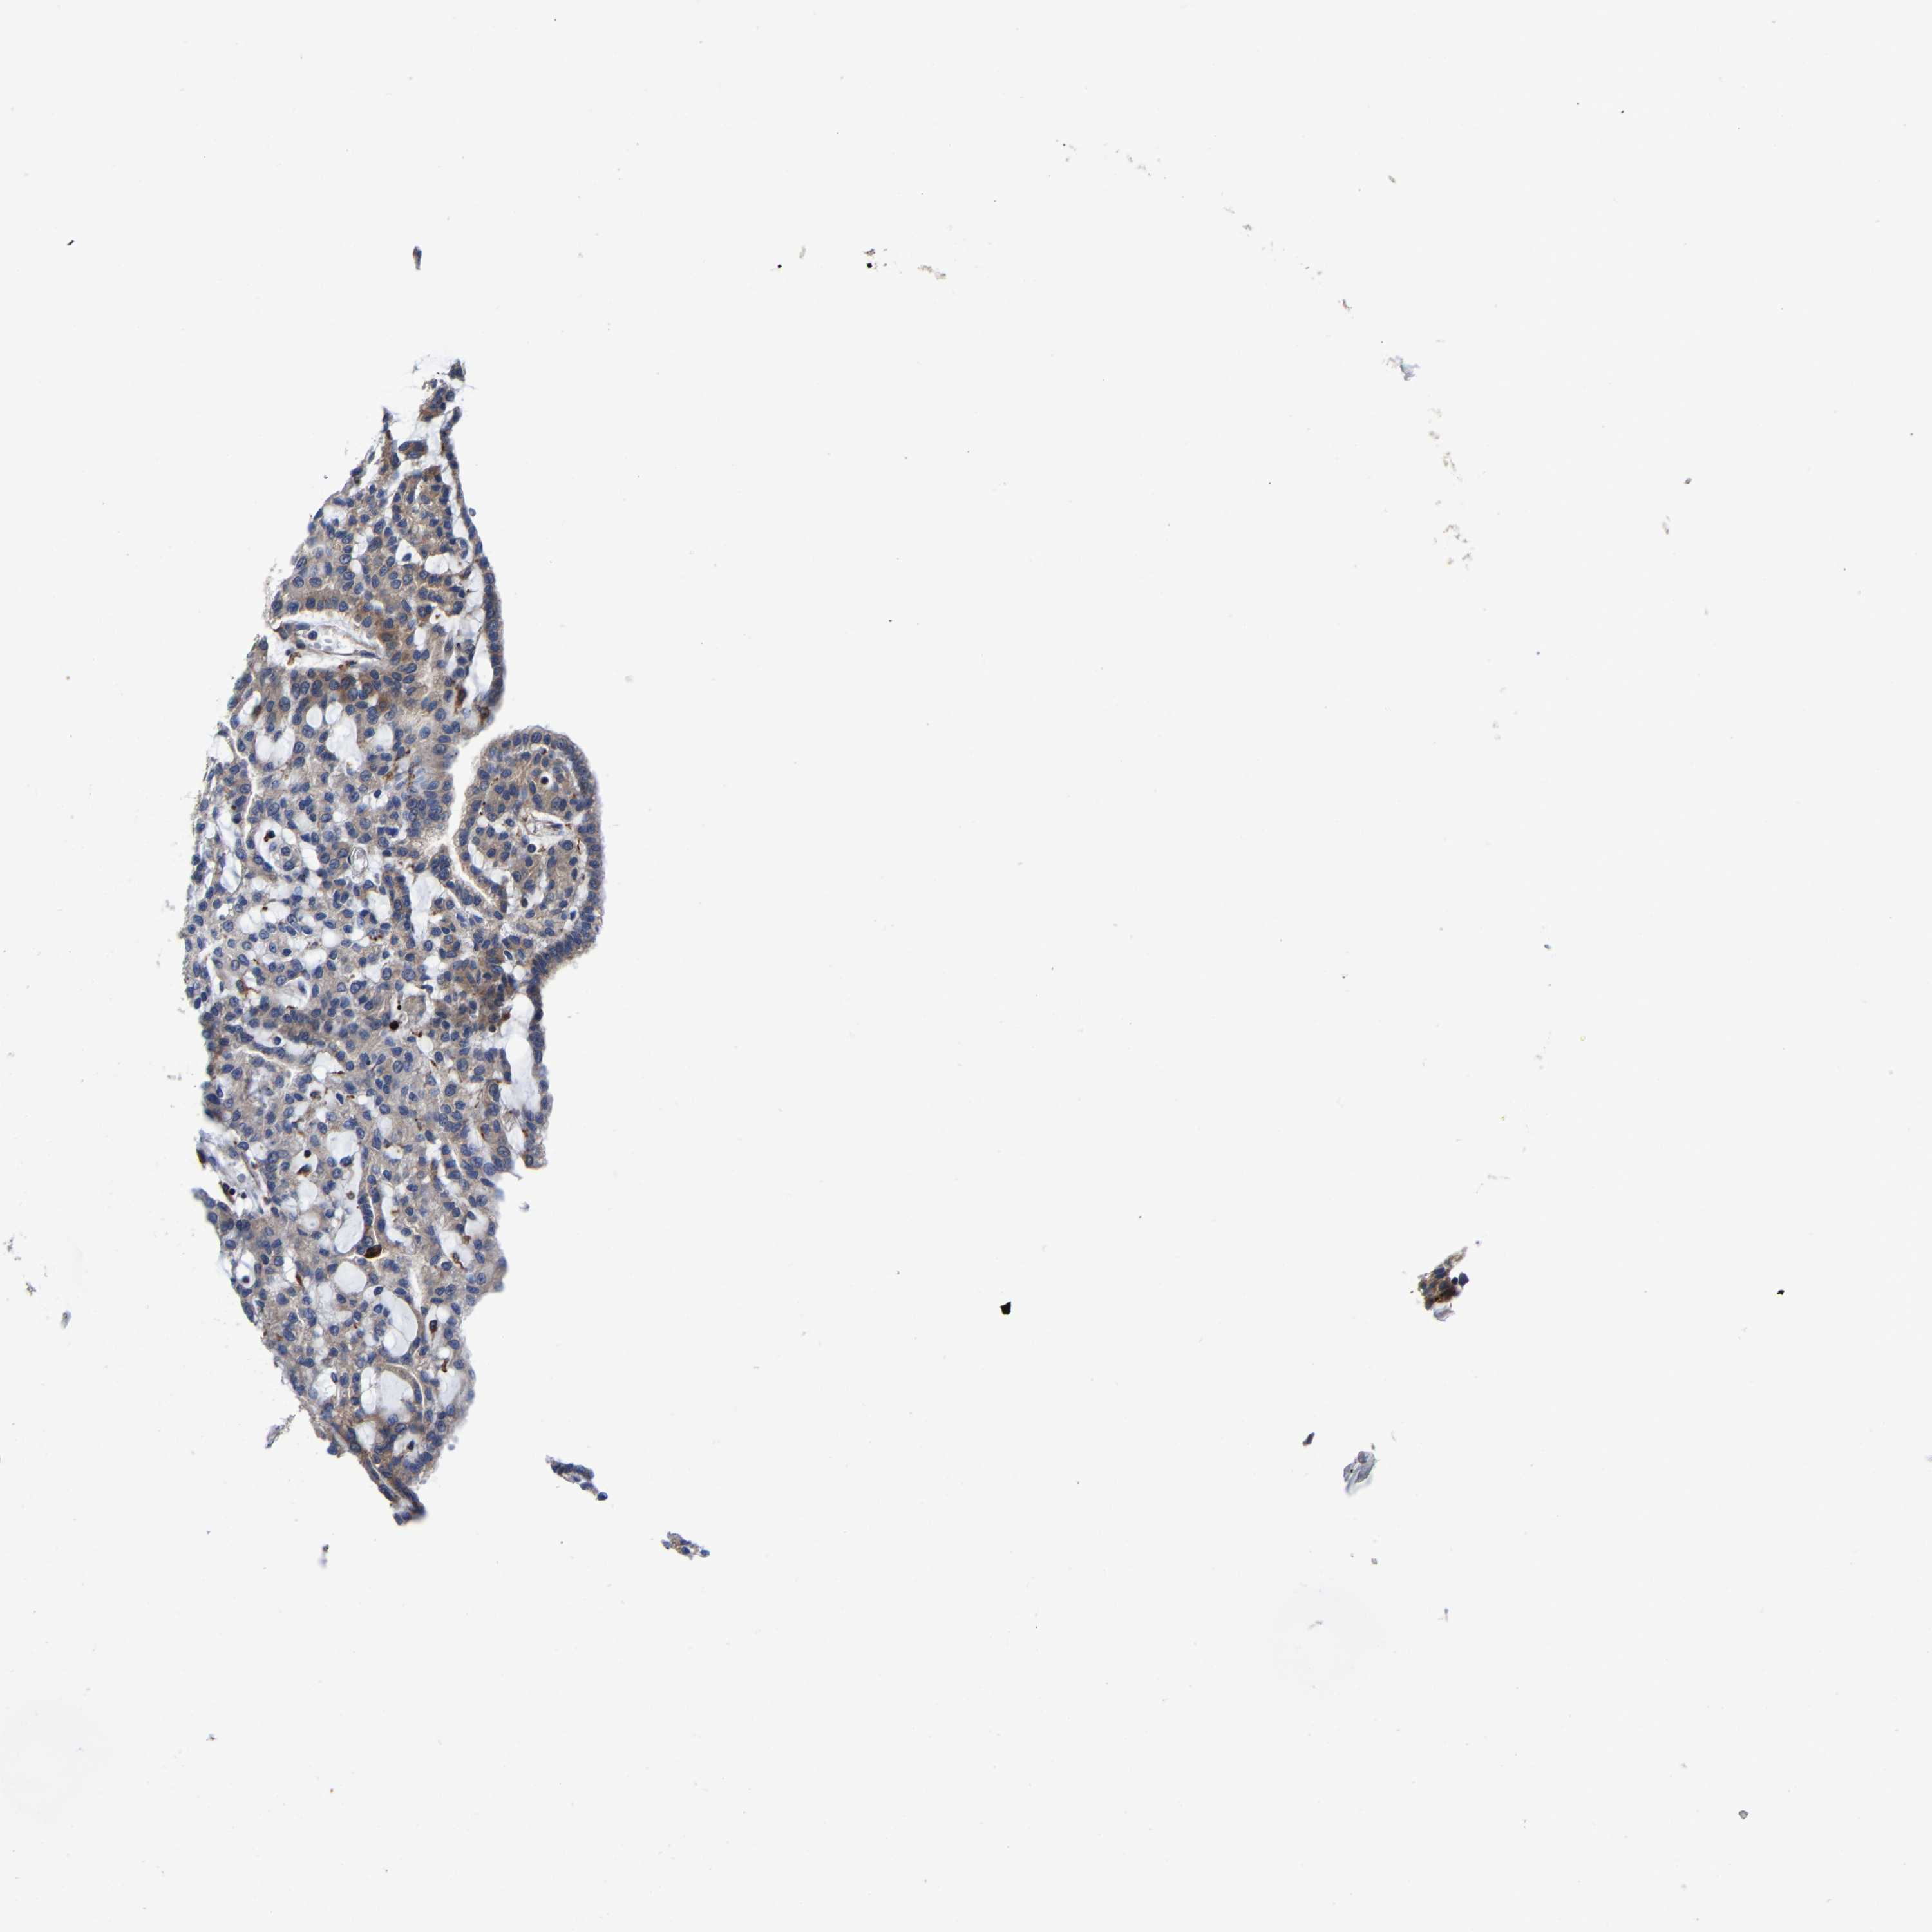

KIDNEY RENAL CLEAR CELL CARCINOMA (VALIDATION) - Interactive survival scatter ploti

The Survival Scatter plot shows the clinical status (i.e. dead or alive) for all individuals in the patient cohort, based on the same data that underlies the corresponding Kaplan-Meier plots. Patients that are alive at last time for follow-up are shown in blue and patients who have died during the study are shown in red.

The x-axis shows the expression levels (FPKM) of the investigated gene in the tumor tissue at the time of diagnosis. The y-axis shows the follow-up time after diagnosis (years). Both axes are complimented with kernel density curves demonstrating the data density over the axes. The top density plot shows the expression levels (FPKM) distribution among dead (red) and alive patients (blue). The right density plot shows the data density of the survived years of dead patients with high and low expression levels respectively, stratified using the cutoff indicated by the vertical dashed line through the Survival Scatter plot. This cutoff is automatically defined based on the FPKM cutoff that minimizes the p-score. The cutoff can be changed by dragging the vertical line or by entering a cutoff value in the square labeled "Current cut-off".

Under the Survival Scatter plot the p-score landscape (black curve; left axis) is shown together with dead median separation (red curve; right axis). Dead median separation is the difference in median mRNA expression between patients who have died with high and low expression, respectively. It is calculated as follows: median FPKM expression of dead patients with high expression - median FPKM expression of dead patients with low expression. This is intended to aid the user in visually exploring custom cutoffs and the associated p-scores and dead median separation.

Individual patient data is displayed and can be filtered by clicking on one or more of the category buttons on the top of the page. Categories describing expression level and patient information include: high, low, alive, dead, female, male and tumor stages. The scale of the x-axis can be toggled between linear and log-scale by clicking on the "x log" button. Mouse-over function shows TCGA ID, patient information and mRNA expression (FPKM) for each patient.

& Survival analysisi

Kaplan-Meier plots summarize results from analysis of correlation between mRNA expression level and patient survival. Patients were divided based on level of expression into one of the two groups "low" (under cut off) or "high" (over cut off). X-axis shows time for survival (years) and y-axis shows the probability of survival, where 1.0 corresponds to 100 percent.

PFKFB3 is not prognostic in Kidney Renal Clear Cell Carcinoma (validation)

Best expression cut offi

Based on the FPKM value of each gene, patients were classified into two groups and association between prognosis (survival) and gene expression (FPKM) was examined. The best expression cut-off refers the FPKM value that yields maximal difference with regard to survival between the two groups at the lowest log-rank P-value. Best expression cut-off was selected based on survival analysis .

When clicking on this number, the vertical dashed line indicating cut-off, the interactive survival plot, and the Kaplan-Meier curve will be adjusted to show results based on the best expression cut-off.

: 76.91

P scorei

Log-rank P value for Kaplan-Meier plot showing results from analysis of correlation between mRNA expression level and patient survival.

N/A

TCGA RNA samplesi

RNA-seq data is reported as average FPKM (number Fragments Per Kilobase of exon per Million reads), generated by the The Cancer Genome Atlas (TCGA) .

Normal distribution across the dataset is visualized with box plots, shown as median and 25th and 75th percentiles. Points are displayed as outliers if they are above or below 1.5 times the interquartile range. FPKM values of the individual samples are presented next to the box plot.

Average pTPM 132.0

Number of samples 100